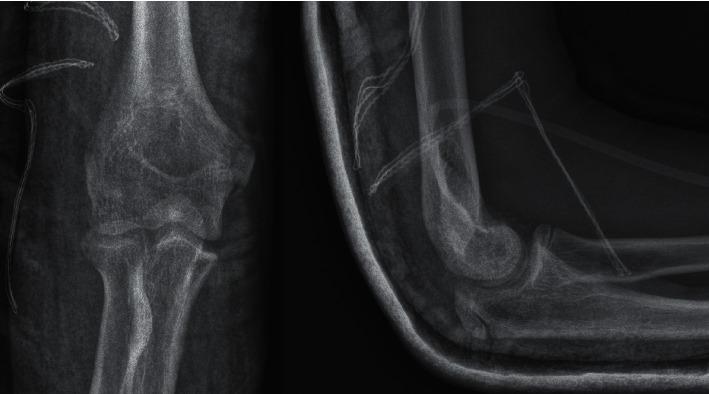

青少年肱骨小头骨折:6例采用可吸收钉切开复位内固定治疗的研究

Humeral Capitellum Fractures in Adolescents: A Study of 6 Cases Treated by Open Reduction and Internal Fixation with Bioabsorbable Nails.

The purpose of our study was to evaluate the clinical outcome following open reduction and internal fixation of humeral capitellum fractures in adolescents and to assess the usefulness of bioresorbable implants in that procedure. Due to the rarity of these fractures, there are not many studies dealing with the problem in the literature.

METHODS

We retrospectively evaluated a group of 6 skeletally immature patients aged 10.6-15.3 treated at our department from January 2015 to December 2021. Four type I and two type IV were diagnosed based on the Bryan and Morrey classification. Our patients underwent an open reduction and internal fixation of coronal shear fractures with the use of SmartNail®.

RESULTS

All patients were satisfied with the treatment outcome and had full pronation and flexion after surgery. Two patients presented minor deficits of extension and supination compared with the contralateral elbow. At the one-year follow-up, all patients scored 100 on the Mayo Elbow Performance Score.

CONCLUSIONS

Correct diagnosis and early surgical intervention in humeral capitellum fractures are crucial. That fractures should be anatomically reduced with no articular cartilage damage in order to prevent osteoarthritis. Based on our experience, SmartNail® implant is accurate for the osteochondral fragment fixation.